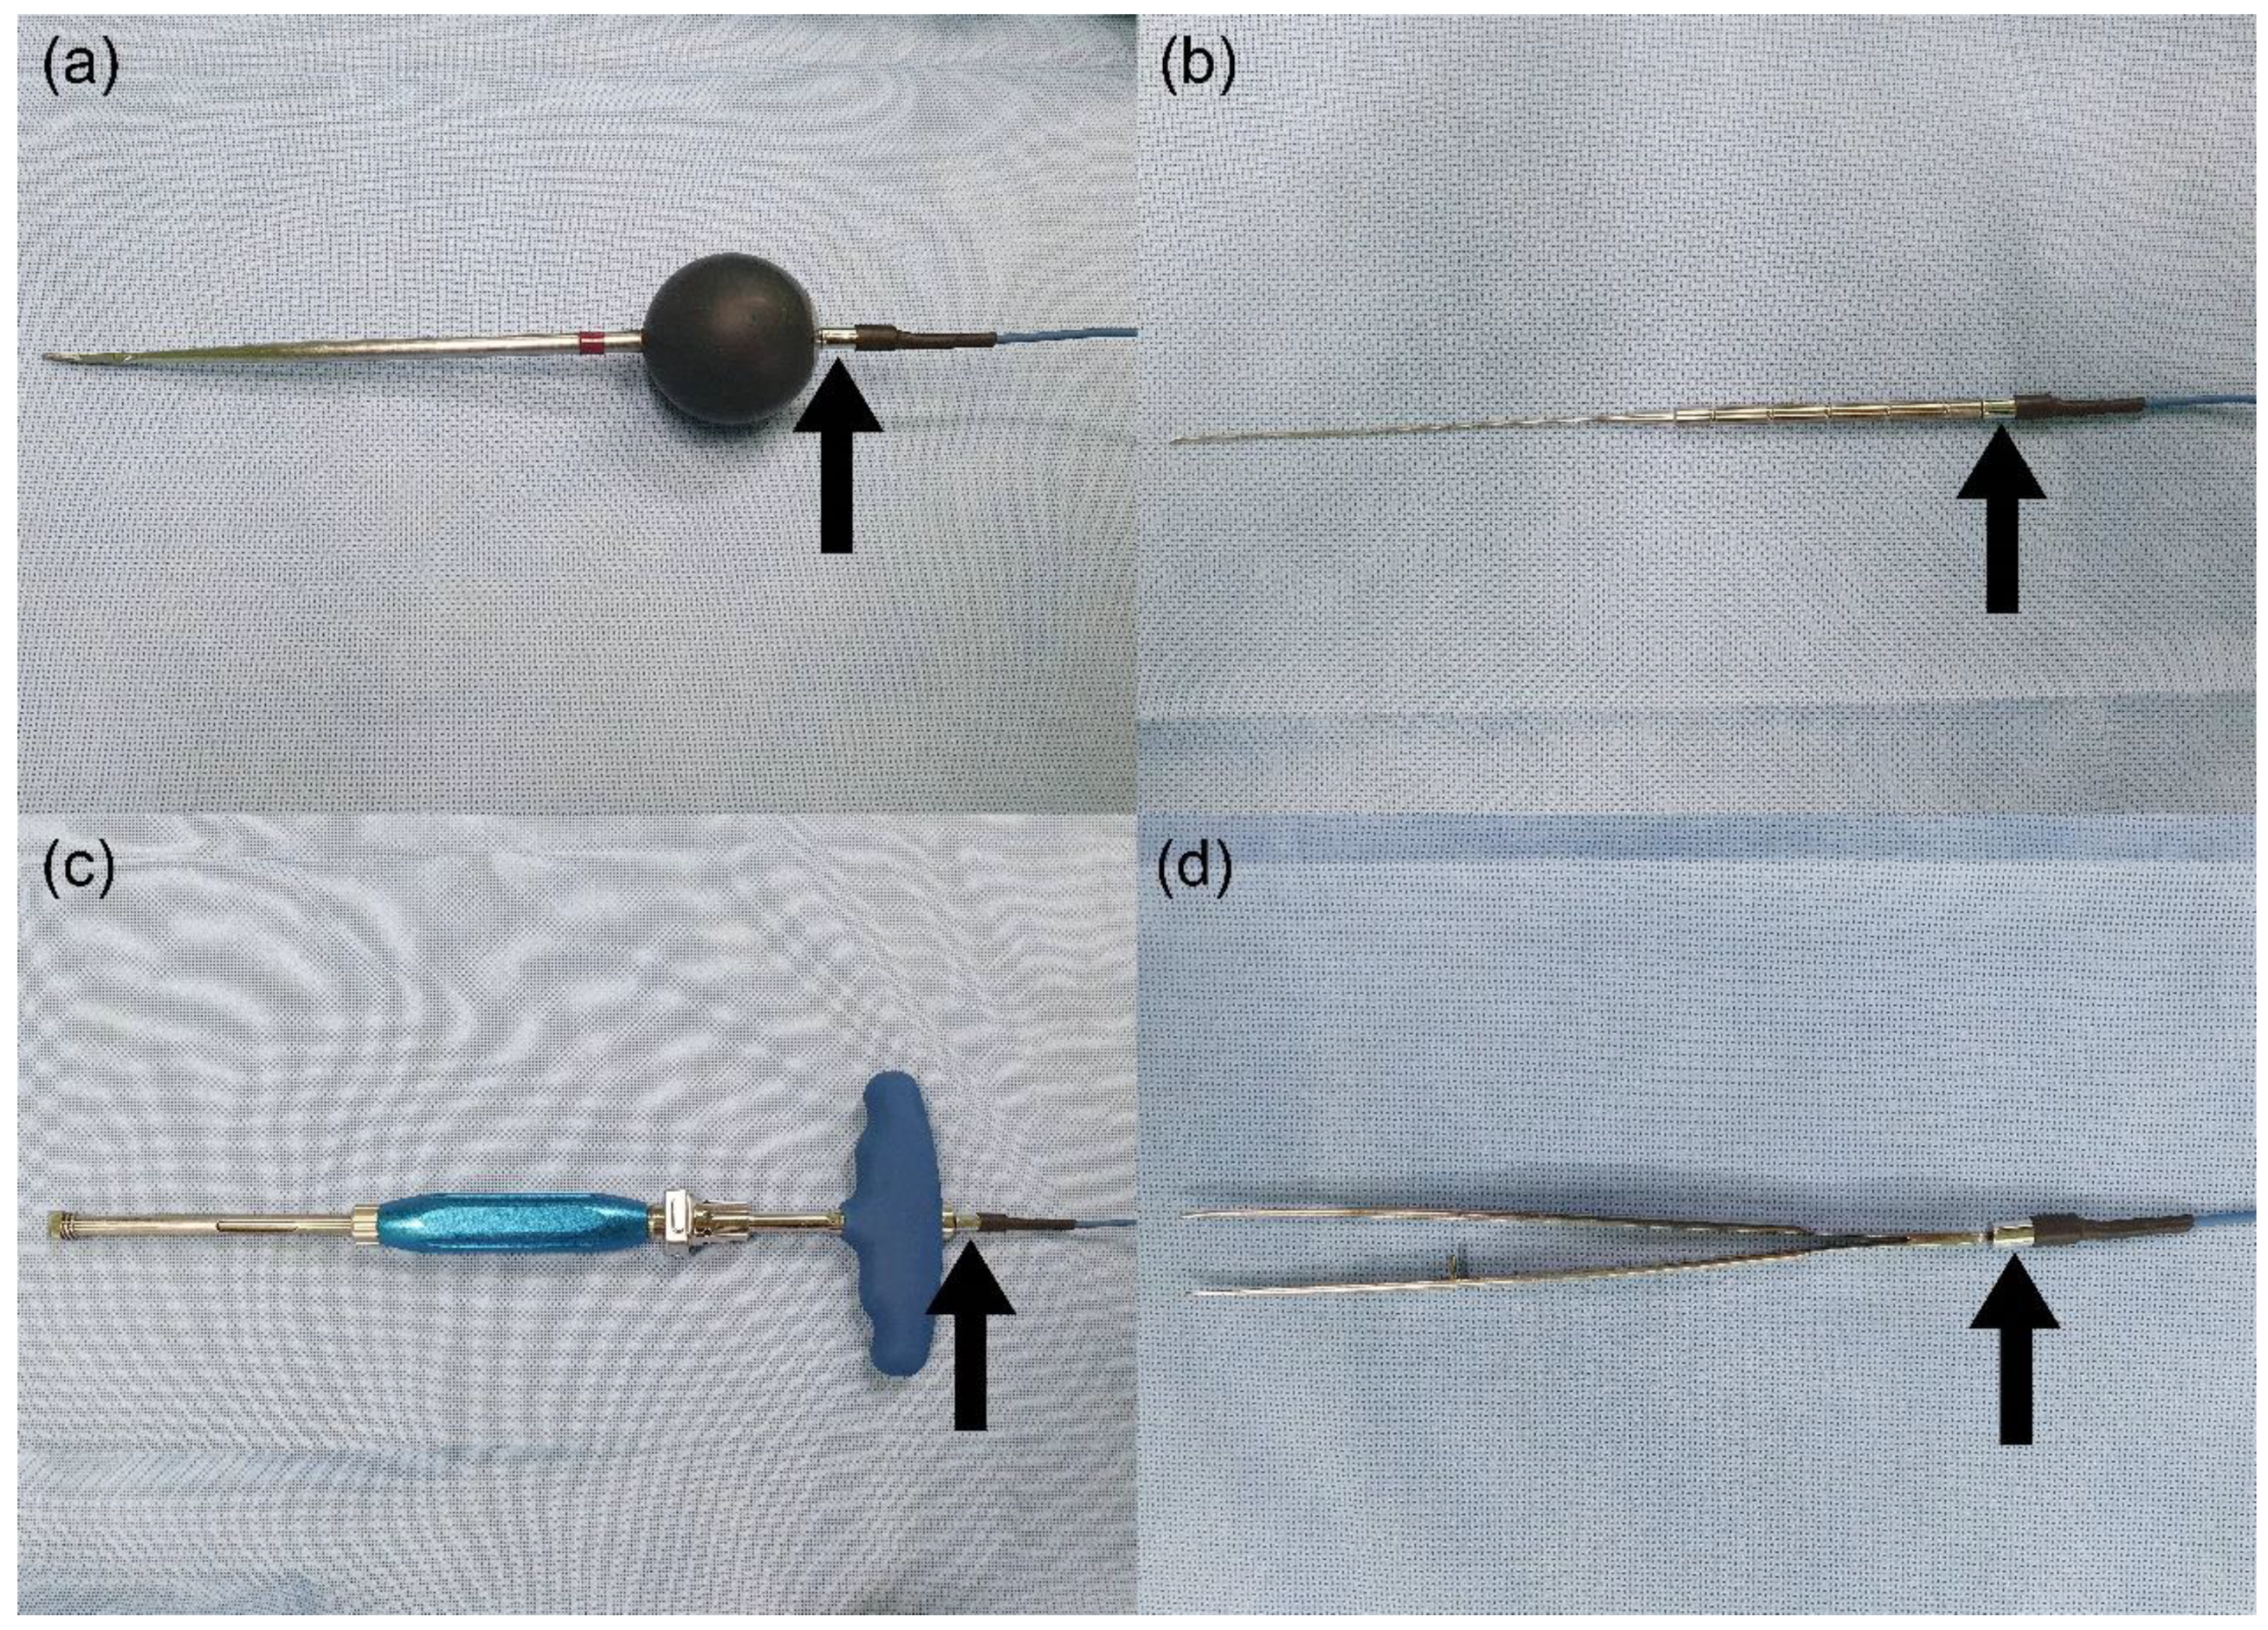

2. Materials and Methods

2.1. Animal Experiment